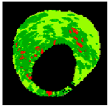

Previous studies have identified texture analysis as being useful in the analysis of ultrasound images. Plaque components appear with different texture patterns in IVUS images (Figure 11). Therefore, texture analysis methods are best suited to classifying pixels from plaque areas of IVUS images into three tissue classes, including dense calcium (DC), necrotic core (NC), and fibro-fatty (FF) [47].

Figure 11.

Different tissue types in the plaque area of IVUS images: (a) dense calcium, (b) necrotic core, and (c) fibro-fatty.